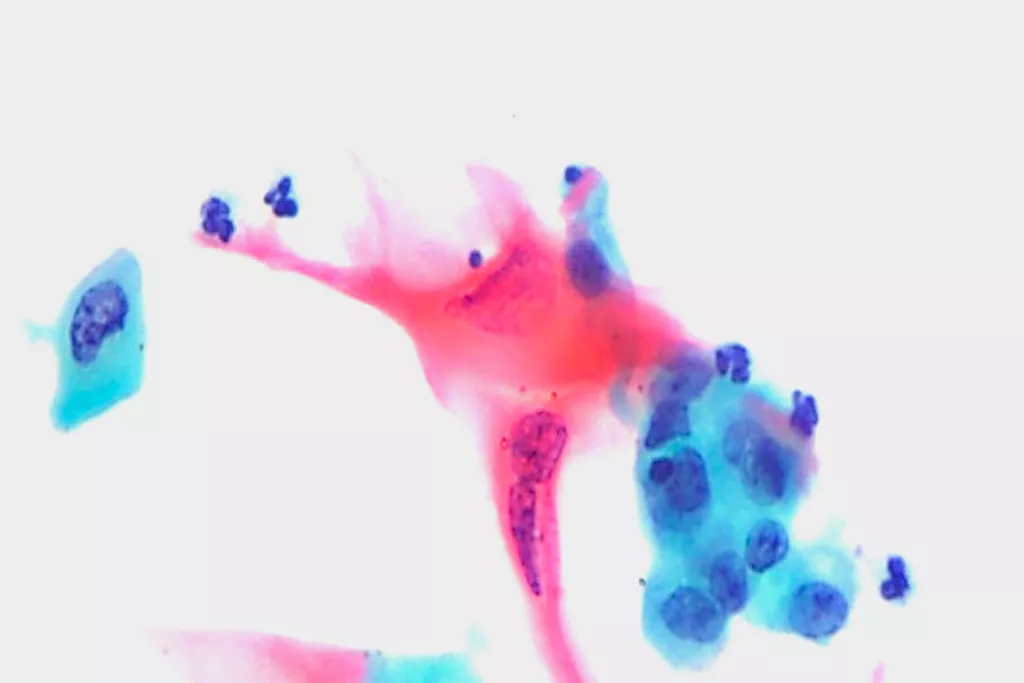

Billedgalleri9

9. Billeder modtaget fra Cytopathology Department, Llandough Hospital, Wales

Troværdige resultater på tværs af alle grader af celleforandringer i livmoderhalsen:

Signifikant mere effektiv end konventionel Pap-smear til påvisning af let grad af pladeepitelforandring (LSIL) og mere alvorlige læsioner (HSIL).2

Forbedret evne til at detektere kirtelsygdom sammenlignet med konventionel Pap.2